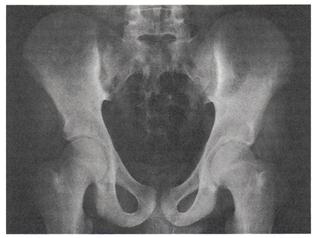

Поскольку первые изменения всегда формируются в области крестцово-подвздошных сочленений, в случае подозрения на АС в обяза­тельном порядке выполняют рентгенограмму таза в передне-задней проекции, захватывающую все кости таза и тазобедренные суставы. Ранний признак сакроилеита — сочетание участков расширения су­ставной щели за счёт эрозий на фоне распространённого субхондрального остеосклероза, сначала со стороны подвздошной кости, а затем и со стороны крестца. Очаговое, а затем полное анкилозирование крестцово-подвздошных сочленений, а также сужение щелей этих су­ставов — поздние признаки сакроилеита (рис. 6-6).

Рис. 6-6. Двусторонний сакроилеитIIIст. (по Келлгрену).